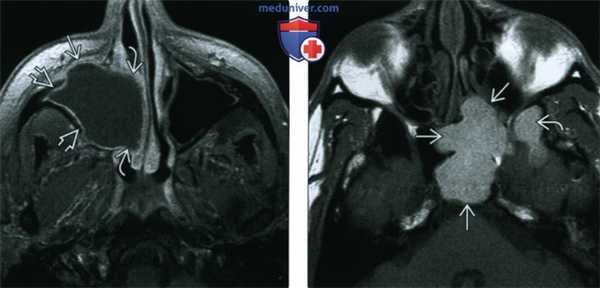

(Слева) При аксиальной МРТ Т1ВИ С+ FS определяется мукоцеле правой верхнечелюстной пазухи с эрозиями передней стенки и распространением кнутри в полость носа. Определяется также периферическое контрастирование слизистой оболочки, но без накопления контраста в центре, что помогает отличить мукоцеле от новообразования.

(Справа) При аксиальной МРТ Т1 визуализируется мукоцеле большого размера в левой основной пазухе, относительно гиперинтенсивное из-за белкового содержимого. Обратите внимание на поражение латерального кармана.